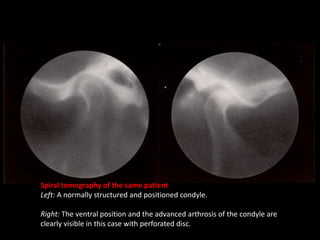

Spiral tomography of the same patient

Left: A normally structured and positioned condyle.

Right: The ventral position and the advanced arthrosis of the condyle are

clearly visible in this case with perforated disc.